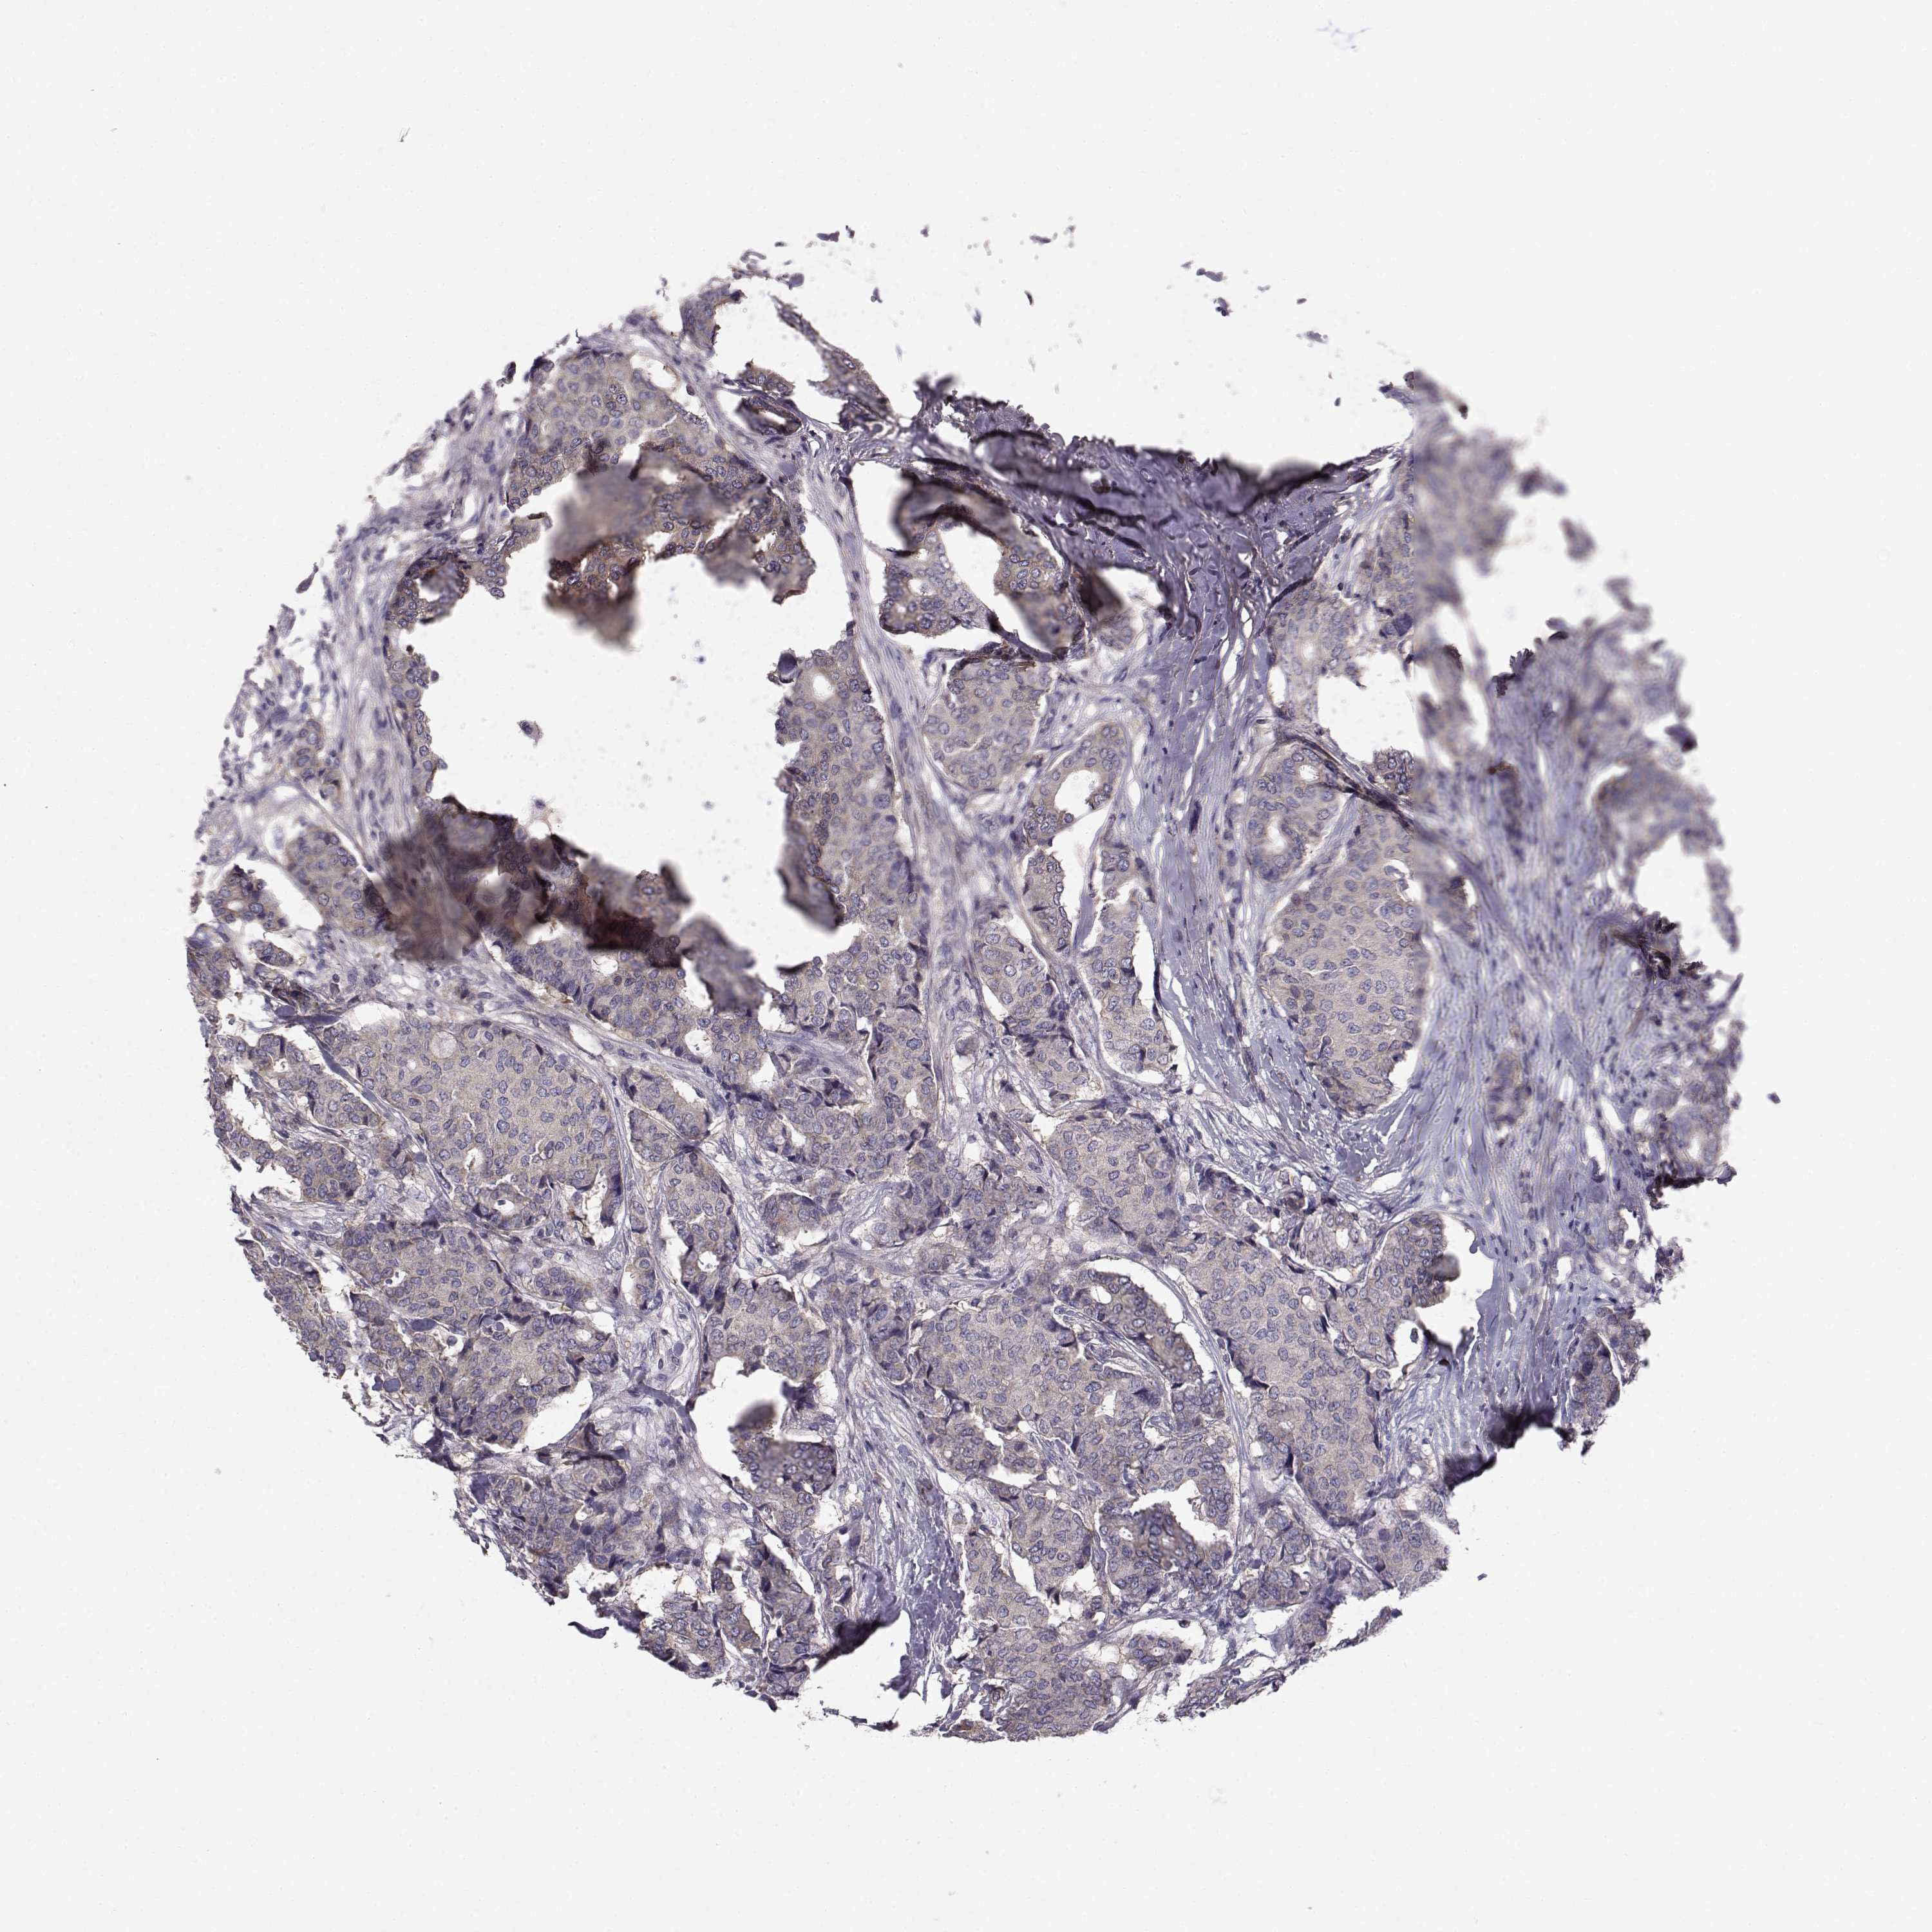

CANCER BREAST CANCER Show tissue menu

BRCA TCGA BRCA VALIDATION PROTEIN EXPRESSION